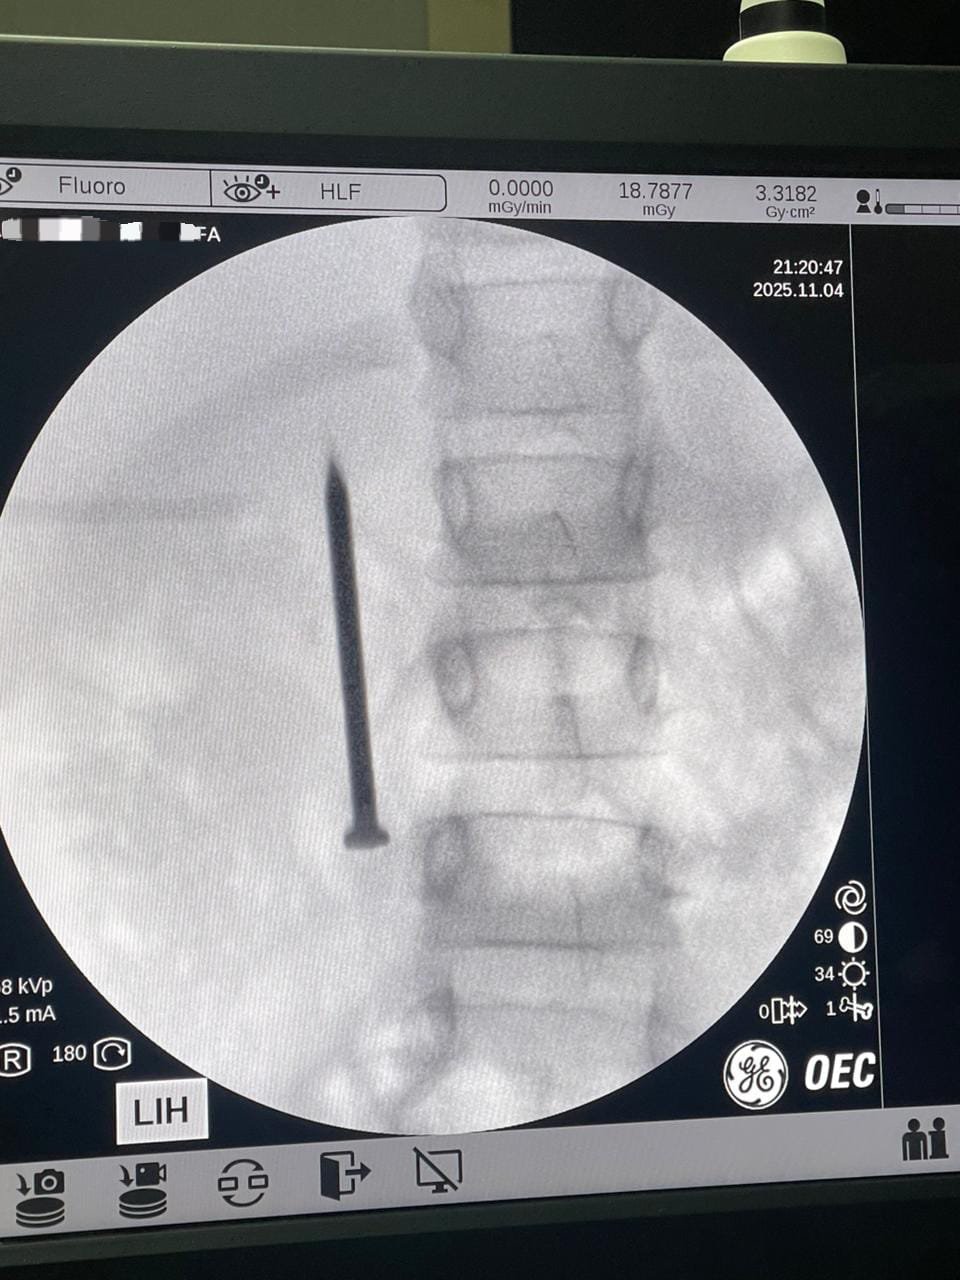

أعلن الدكتور أحمد القاصد، رئيس جامعة المنوفية، عن نجاح فريق طبي متخصص بوحدة مناظير الجهاز الهضمي بمعهد الكبد القومي في إنقاذ حياة طفلة تبلغ من العمر 7 سنوات، بعد ابتلاعها مسمارًا معدنيًا حادًا يبلغ طوله 4 سنتيمترات.

وأوضح رئيس الجامعة أن الفريق الطبي تمكن من استخراج المسمار الذي وصل إلى الجزء الأول من الأمعاء الدقيقة (الصائم) عبر إجراء منظار طارئ لم يستغرق سوى 20 دقيقة، متجنبًا بذلك خطر الثقب أو النزيف أو الانسداد المعوي الوشيك، حيث غادرت الطفلة المستشفى بصحة جيدة بعد التدخل الطبي السريع.

وأشار الدكتور أحمد القاصد إلى أن استخراج المسمار بهذه السرعة وبهذه التقنية الآمنة يعكس الاحترافية العالية لفريق المعهد وقدرته على التعامل مع أصعب الحالات الطارئة التي تهدد حياة الأطفال موجها الشكر للفريق الطبي.

من جانبه، أكد الدكتور أحمد صيرة، أستاذ طب كبد الأطفال ورئيس وحدة مناظير الأطفال وقائد الفريق الطبي، أن استخدام المنظار كان الخيار الأمثل لتجنب إجراء عملية جراحية مفتوحة أكثر إرهاقًا للطفلة، مشددًا على أهمية التدخل السريع في مثل هذه الحالات لتفادي مضاعفات محتملة مثل الثقب أو النزيف أو الانسداد المعوي.

وضم الفريق الطبي الدكتور أحمد صيرة، دكتور هديل درويش (مدرس مساعد)، دكتور حاتم نايل (طبيب مقيم)، دكتور علي التراس (طبيب مقيم)، ومن تمريض وحدة المناظير: دعاء طلعت، أسماء جابر، أستاذ عبد المولى، بالإضافة إلى فريق أطباء التخدير: دكتور دعاء شرف (مدرس مساعد)، دكتور مريم رزق (طبيب مقيم)، دكتور سندس صبري (طبيب مقيم)، ومن تمريض التخدير: محمد بكر، هيثم، ومحمد الشهاوي فني الأشعة.